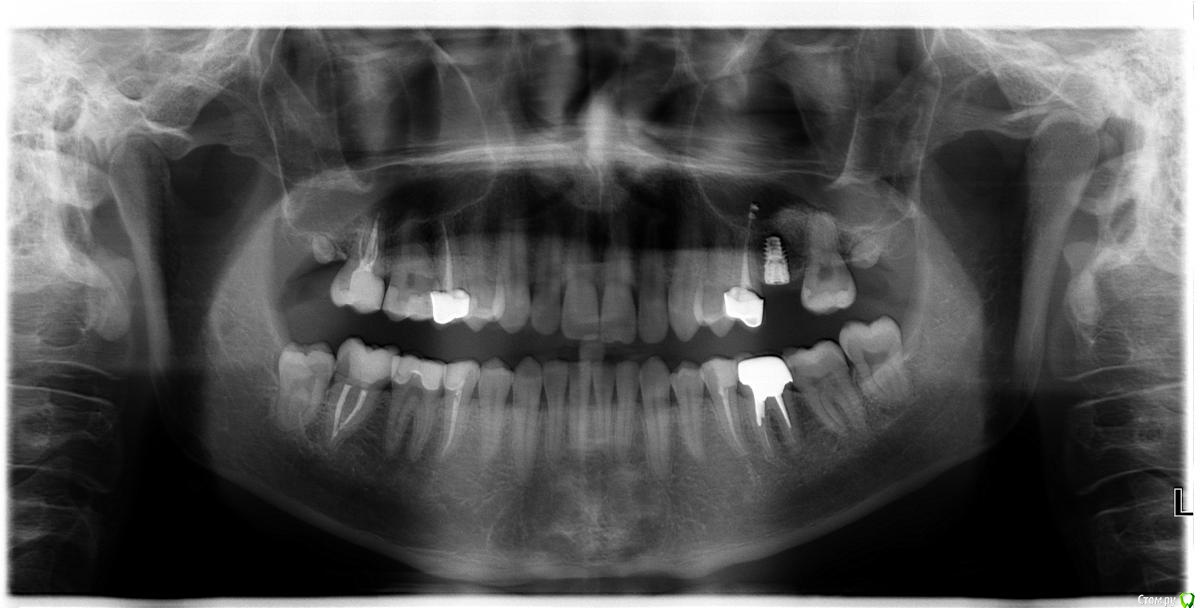

Rusty Опубликовано 26 октября, 2015 Поделиться Опубликовано 26 октября, 2015 Добрый вечер. Коллеги, подскажите что за винт. Устанавливался 1,5 года назад в Москве, бюджет около 35т.р. Ссылка на комментарий

zzkz Опубликовано 27 октября, 2015 Поделиться Опубликовано 27 октября, 2015 очень похоже на израиль либо 4.2, либо с широкой платформой 5.0 Ссылка на комментарий